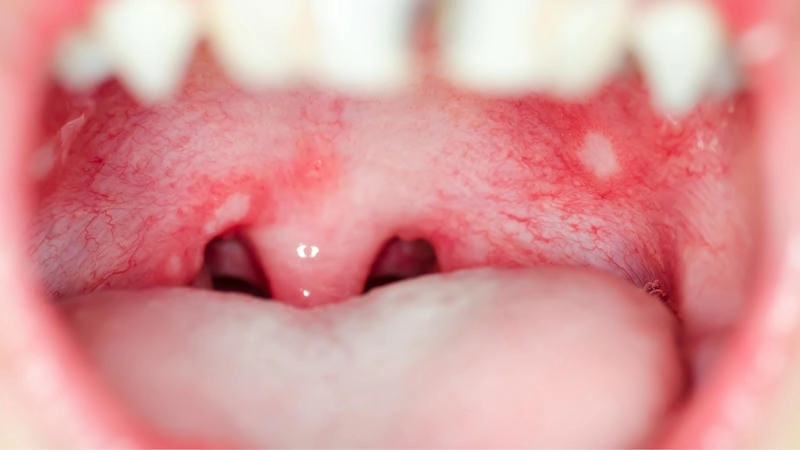

Những hình ảnh bệnh tay chân miệng cấp độ 1 đầu tiên có thể khiến nhiều người chủ quan vì triệu chứng nhìn qua tưởng chỉ là vết muỗi đốt. Nhưng đằng sau đó là nguy cơ lây lan nhanh, nhất là ở trẻ nhỏ. Từ các nốt hồng ban li ti ở lòng bàn tay, bàn chân cho tới vài mụn nước nhỏ ở quanh miệng – tất cả đều là dấu hiệu sớm cần nhận biết. Việc nhìn rõ những hình ảnh ở giai đoạn đầu là cách cảnh báo sớm, ngăn bệnh tiến triển sang cấp độ nguy hiểm hơn.

Tổng hợp ảnh tay chân miệng cấp độ 1 mang đến cái nhìn chân thực, không hề che giấu về diễn biến ban đầu của căn bệnh tưởng chừng vô hại này. Qua loạt ảnh cận cảnh, bạn sẽ thấy rõ các nốt mụn li ti xuất hiện rải rác nhưng có quy luật, tập trung ở những vùng dễ bị bỏ qua. Đừng xem thường – chỉ một vài nốt nhỏ có thể là dấu hiệu của cơn bùng phát sắp tới. Đây chính là kho tư liệu quý giá cho phụ huynh và nhân viên y tế nhận diện sớm và phản ứng kịp thời.